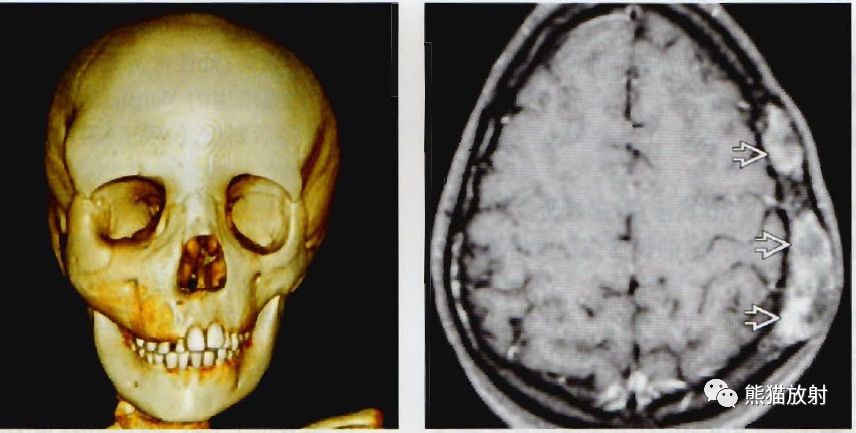

骨肿瘤样病变的影像学诊断之paget病与abc